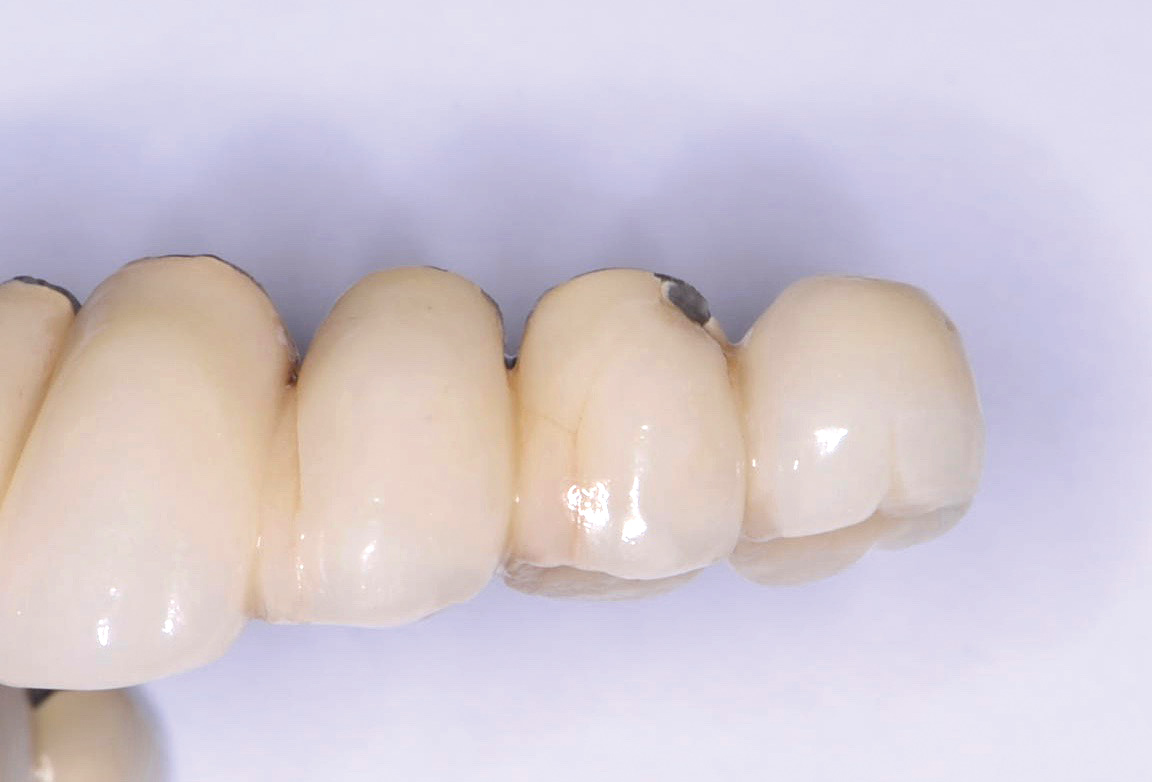

Fig 10. Fractured zirconia abutment with a titanium base.

Figure 10

Fig 11. Fractured all-zirconia abutment.

Figure 11

The increase in demand for esthetically pleasing implant restorations has led clinicians to embrace the use of all-ceramic abutments. This has subsequently increased abutment fractures (Figure 10 and Figure 11)22,23 and decementation of the ceramic crown and corresponding abutment.24 Use of zirconia abutments is relatively new in implant dentistry and has limited long-term follow-up data. Time will tell whether this technology is successful.